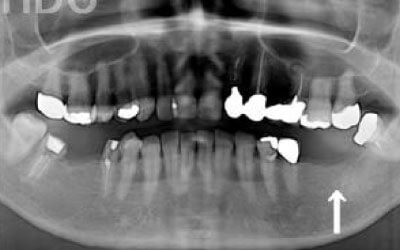

ブリッジとインプラントの大きな違いは、前後の歯の寿命に大きく関わることです。

ブリッジ治療では、抜けた歯の両隣を土台とするため、健康な歯でも大きく削る必要があり、負担がかかります。

また、失った歯の噛む力を前後の2本で支えるため、通常の約1.5倍の力がそれぞれにかかることになります。

1)ブリッジ治療

2)健康な隣の歯を大きく削る+支える歯に通常以上の力がかかる

3)結果として、両隣の歯の寿命が短くなる

実際に、支えとなる歯の約68%が10年以内に抜歯に至るというデータもあります。